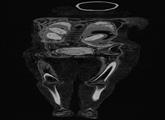

囧!埃及舞女木乃伊CT扫描发现竟是男儿身

近来,研究团队对一具1835年收藏进大英博物馆的埃及木乃伊进行了CT扫描,结果令人大吃一惊。 据大英博物馆古埃及与苏丹文化部门负责人John Taylor介绍,这具木乃伊刚被发现时,人们观察到其胸部...【